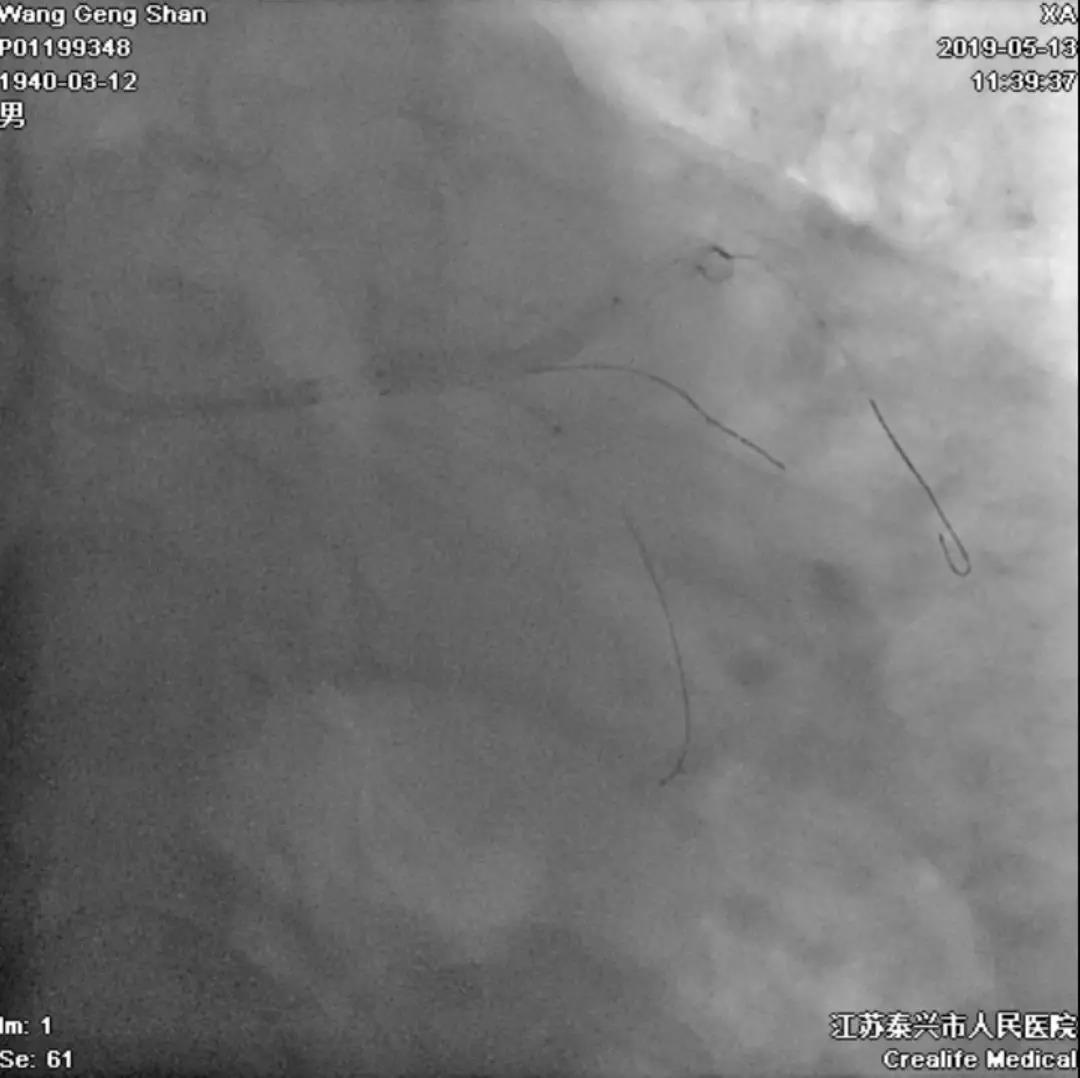

05 LM-LAD支架植入

右头位定位

蜘蛛位定位

LCX球囊拘禁,主支支架释放

回撤LCX球囊